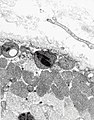

EM

Features:

- Crystalloid inclusions.[26]

- "Ballooned" mitochondria; loss of cristae -- loss of membranous folds within mitochrondrion.

- Endothelial tubuloreticular inclusions (abbrev. TRIs) - undulating tubules in the smooth ER, usu. perinuclear;[29] not pathognomonic - may be seen in inclusion body myositis.[30]